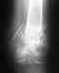

С апреля месяца очень болит нога.Болевые ощущения наблюдаются от поясницы до нижней конечности ноги. При ходьбе боль немного утихает, но в положении сидя/лежа начинается вновь.

боли носят ноющий, тянущий характер. В положении сидя нога от бедра до щиколотки немеет.Очень тяжело и больно вставать утром с постели. Рентгенологическое обследование показало - задний подвывих позвонка(?), но в ближайшее время никаких травм не было. Прошла курс лечения у терапевта, невролога, курс массажа - улучшений никаких. Посоветуйте, пожалуйста, что делать!?